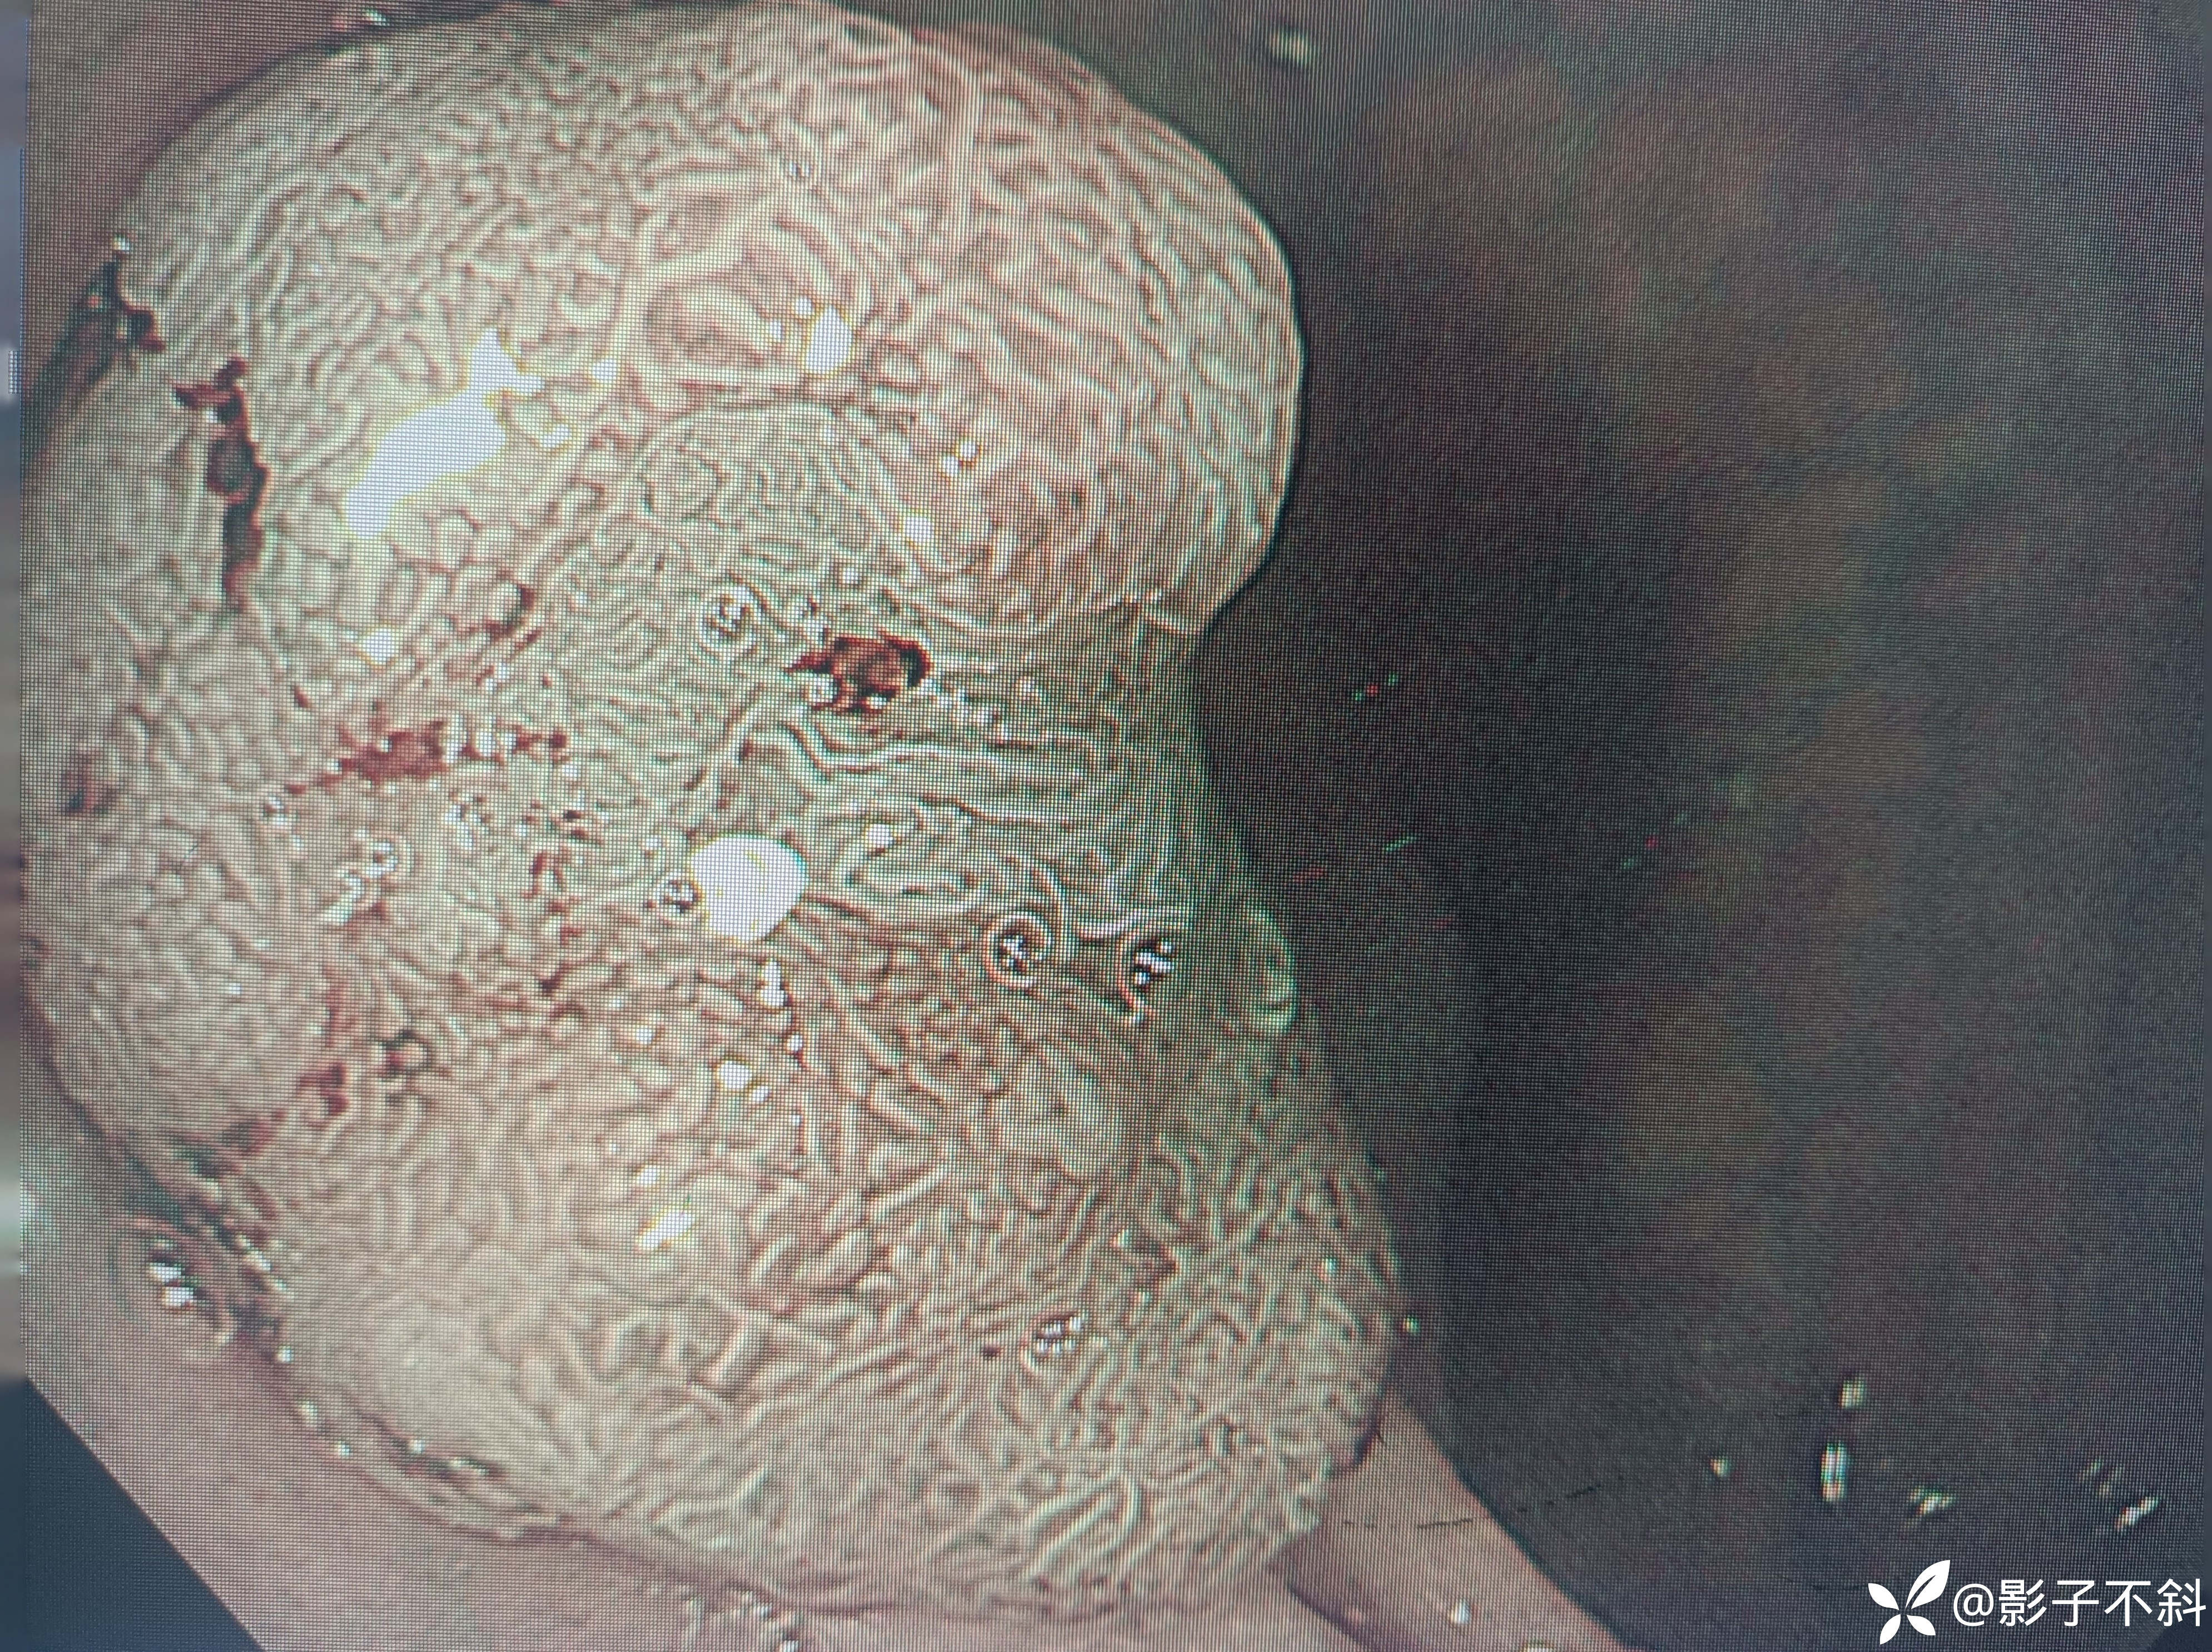

直肠见如下病变